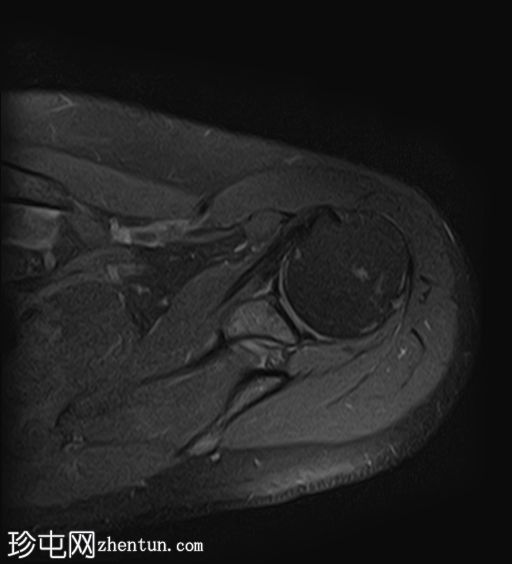

X线片

1.png

正位

冈上肌腱止点处可见弧形钙化,符合钙化性肌腱炎的影像学表现

未见相关骨骼异常